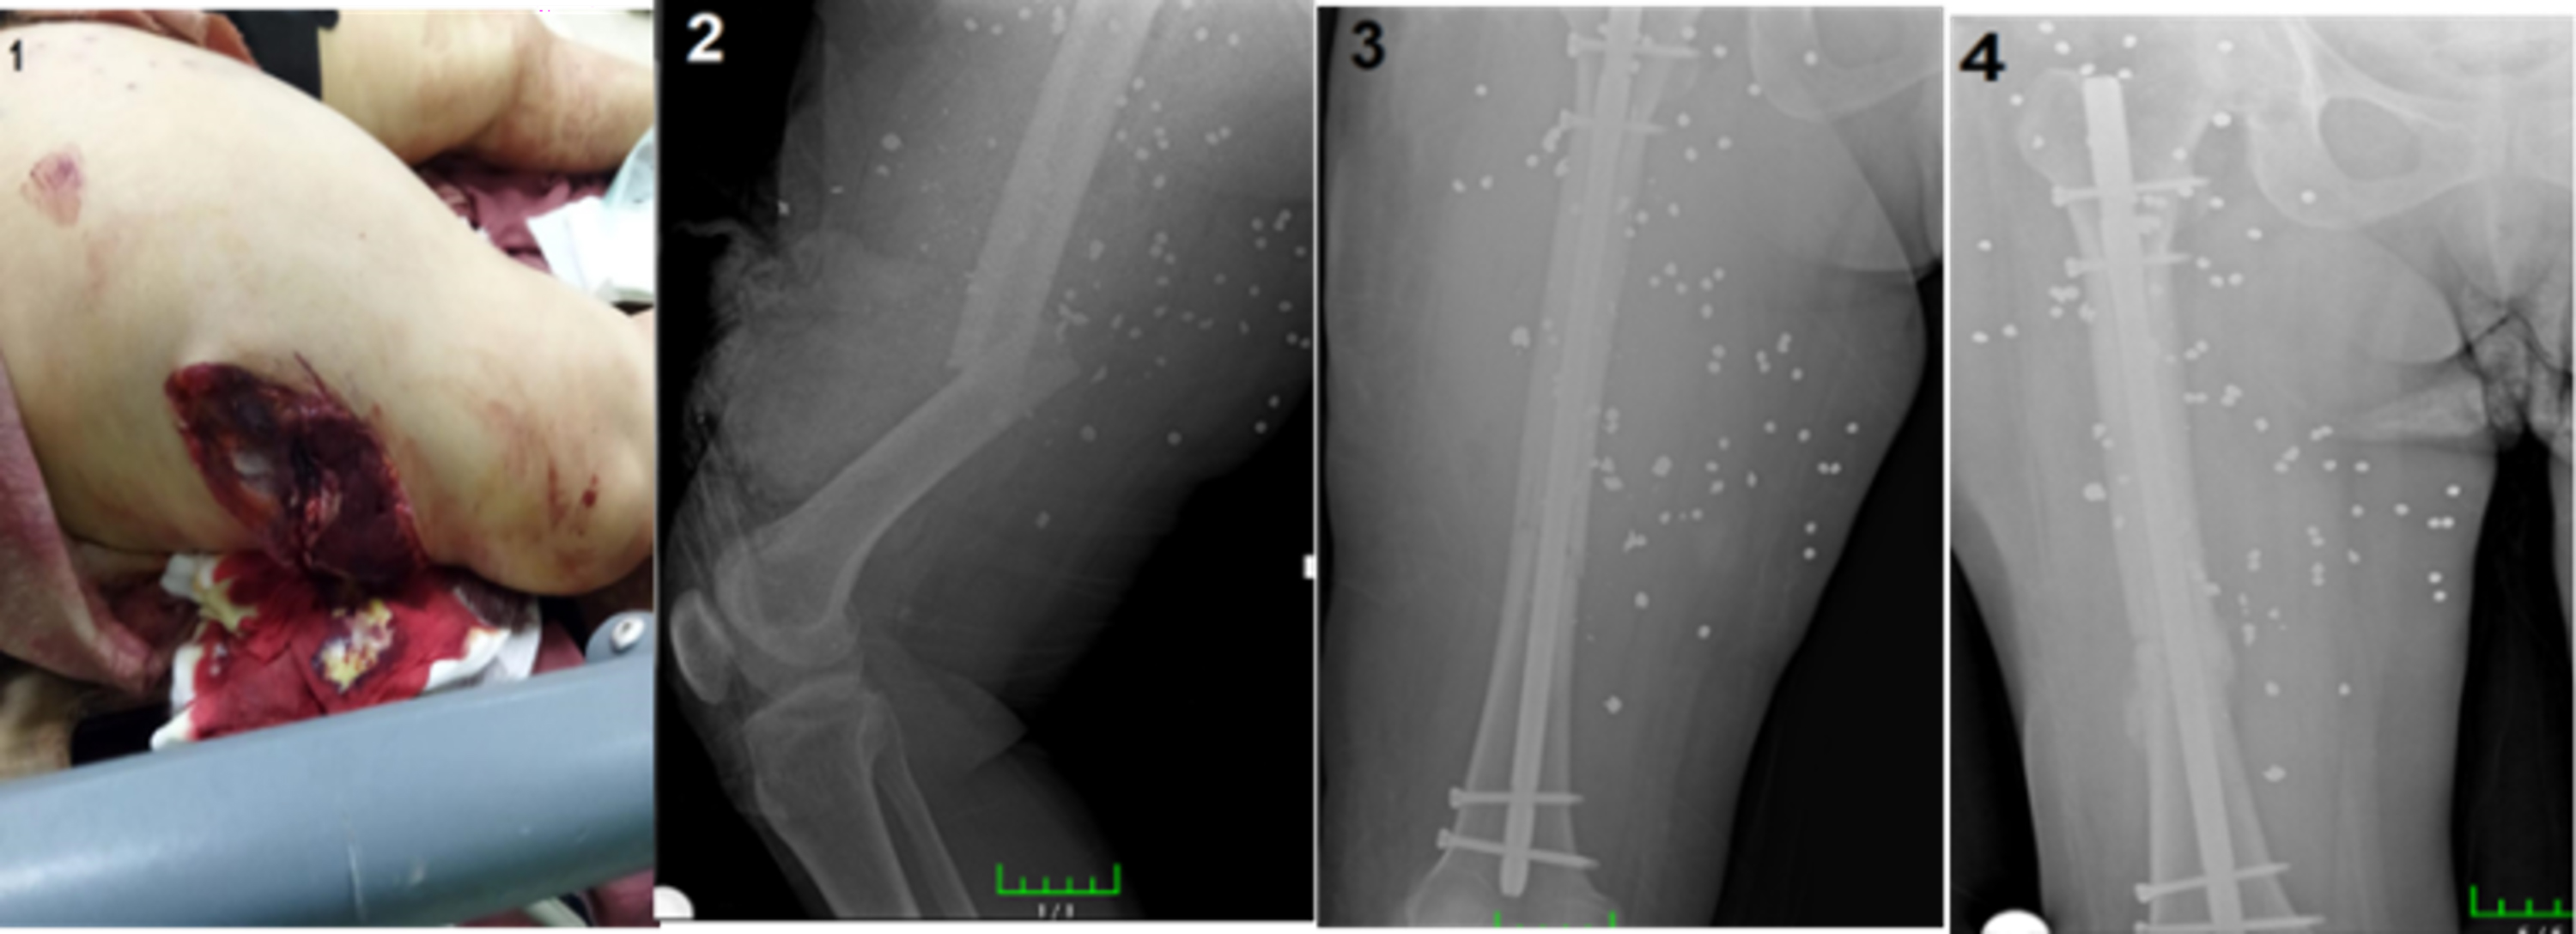

In a study conducted by Mian Amjad Ali and colleagues involving 68 patients with femoral fractures resulting from high-velocity gunshot injuries treated with locked intramedullary nails, the average union time was reported as 24 weeks, with nonunion observed in 4 cases (5.88%).16 We applied intramedullary nailing to 48 femoral shaft fractures, the majority of which occurred as a result of high-velocity gunshot injuries, and calculated the average union time as 19.2 weeks. Nonunion was observed in 3 patients (6.25%). We attribute this relatively shorter union time to the young patient profile, early weight bearing, and our experience in war surgery. Representative preoperative and postoperative radiographs of femoral fractures treated with intramedullary nailing are shown in Figure 3.

Figure 3

Figure 3. (1)Femur Fracture - Preoperative Radiograph (2) Postoperative Radiograph of Femoral Intramedullary Nailing (3) Type 3C Femur Fracture with Vascular Injury